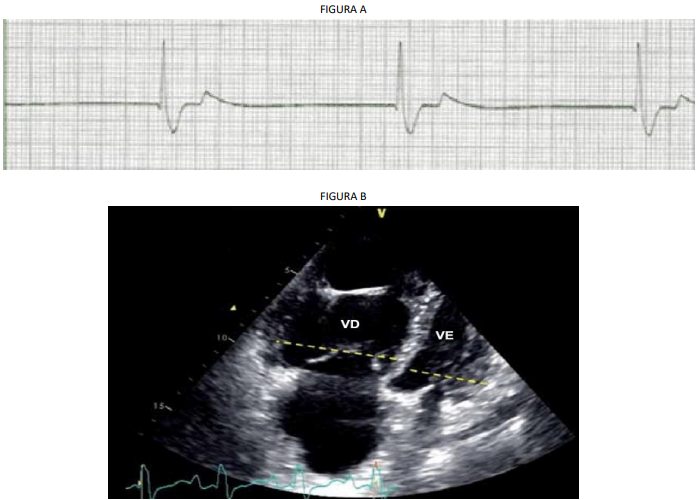

No quinto dia de pós-operatório apresentou episódio de perda súbita da consciência ao se levantar do leito. Foi prontamente atendida, não sendo identificado pulso carotídeo palpável. Iniciadas manobras de ressuscitação e instalada monitorização cardíaca que mostrou o ritmo identificado na figura A. Após 6 minutos houve recuperação da circulação espontânea, em taquicardia sinusal. Ao exame não respondia a comandos verbais ou estímulos dolorosos, com PA: 80×50 mmHg e FC: 120 bpm, além de turgência jugular patológica e ausculta respiratória sem alterações. Bem adaptada à ventilação mecânica, porém com uma saturação de O2 de 85% na vigência de uma FiO2 de 100%. Radiografia de tórax sem alterações parenquimatosas e com tubo orotraqueal bem posicionado.

Um ecocardiograma transtorácico de urgência foi realizado, mostrando pressão sistólica da artéria pulmonar de 78 mmHg e o corte com 4 câmaras encontra-se abaixo (figura B) (VD = ventrículo direito; VE = ventrículo esquerdo).